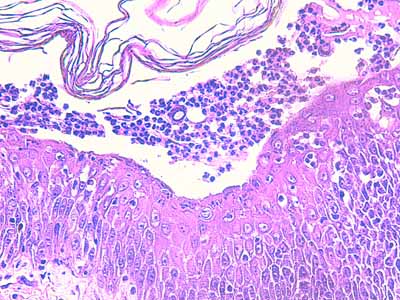

Photo 9 (Hémalun Eosine X 40) : Les pustules sous-cornées qui parsèment l’épiderme,

peuvent ponter l’abouchement de plusieurs follicules pileux voisins.

Légendes de la Photo 9 :

- Double flèche noire : épiderme

- Double flèche pointillée noire : derme

- Pointes de flèche turquoise : délimitation de la pustule intra-épidermique sous-cornée qui ponte l’abouchement de trois unités folliculo-sébacées

- Pointes de flèche jaune : toit rompu de la pustule (fines lamelles de kératine orthokératosique)

- Cercles marrons : glandes sébacées

- Étoiles rouges pleines : vaisseaux sanguins

- Étoiles rouges vides : follicules pileux

- Étoiles turquoises : glandes sudorales apocrines épitrichiales

- Flèche orange : infiltrat dermique de topographie péri-vasculaire